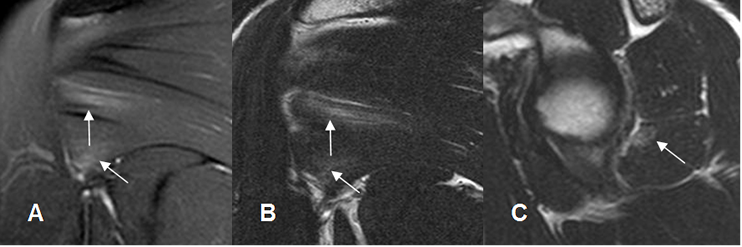

Fig 19. Distensión muscular grado I.

A: RM coronal en STIR, B: RM coronal en T2 y C: RM sagital en T2. Lesión muscular con edema de fibras del redondo menor, sin ruptura.